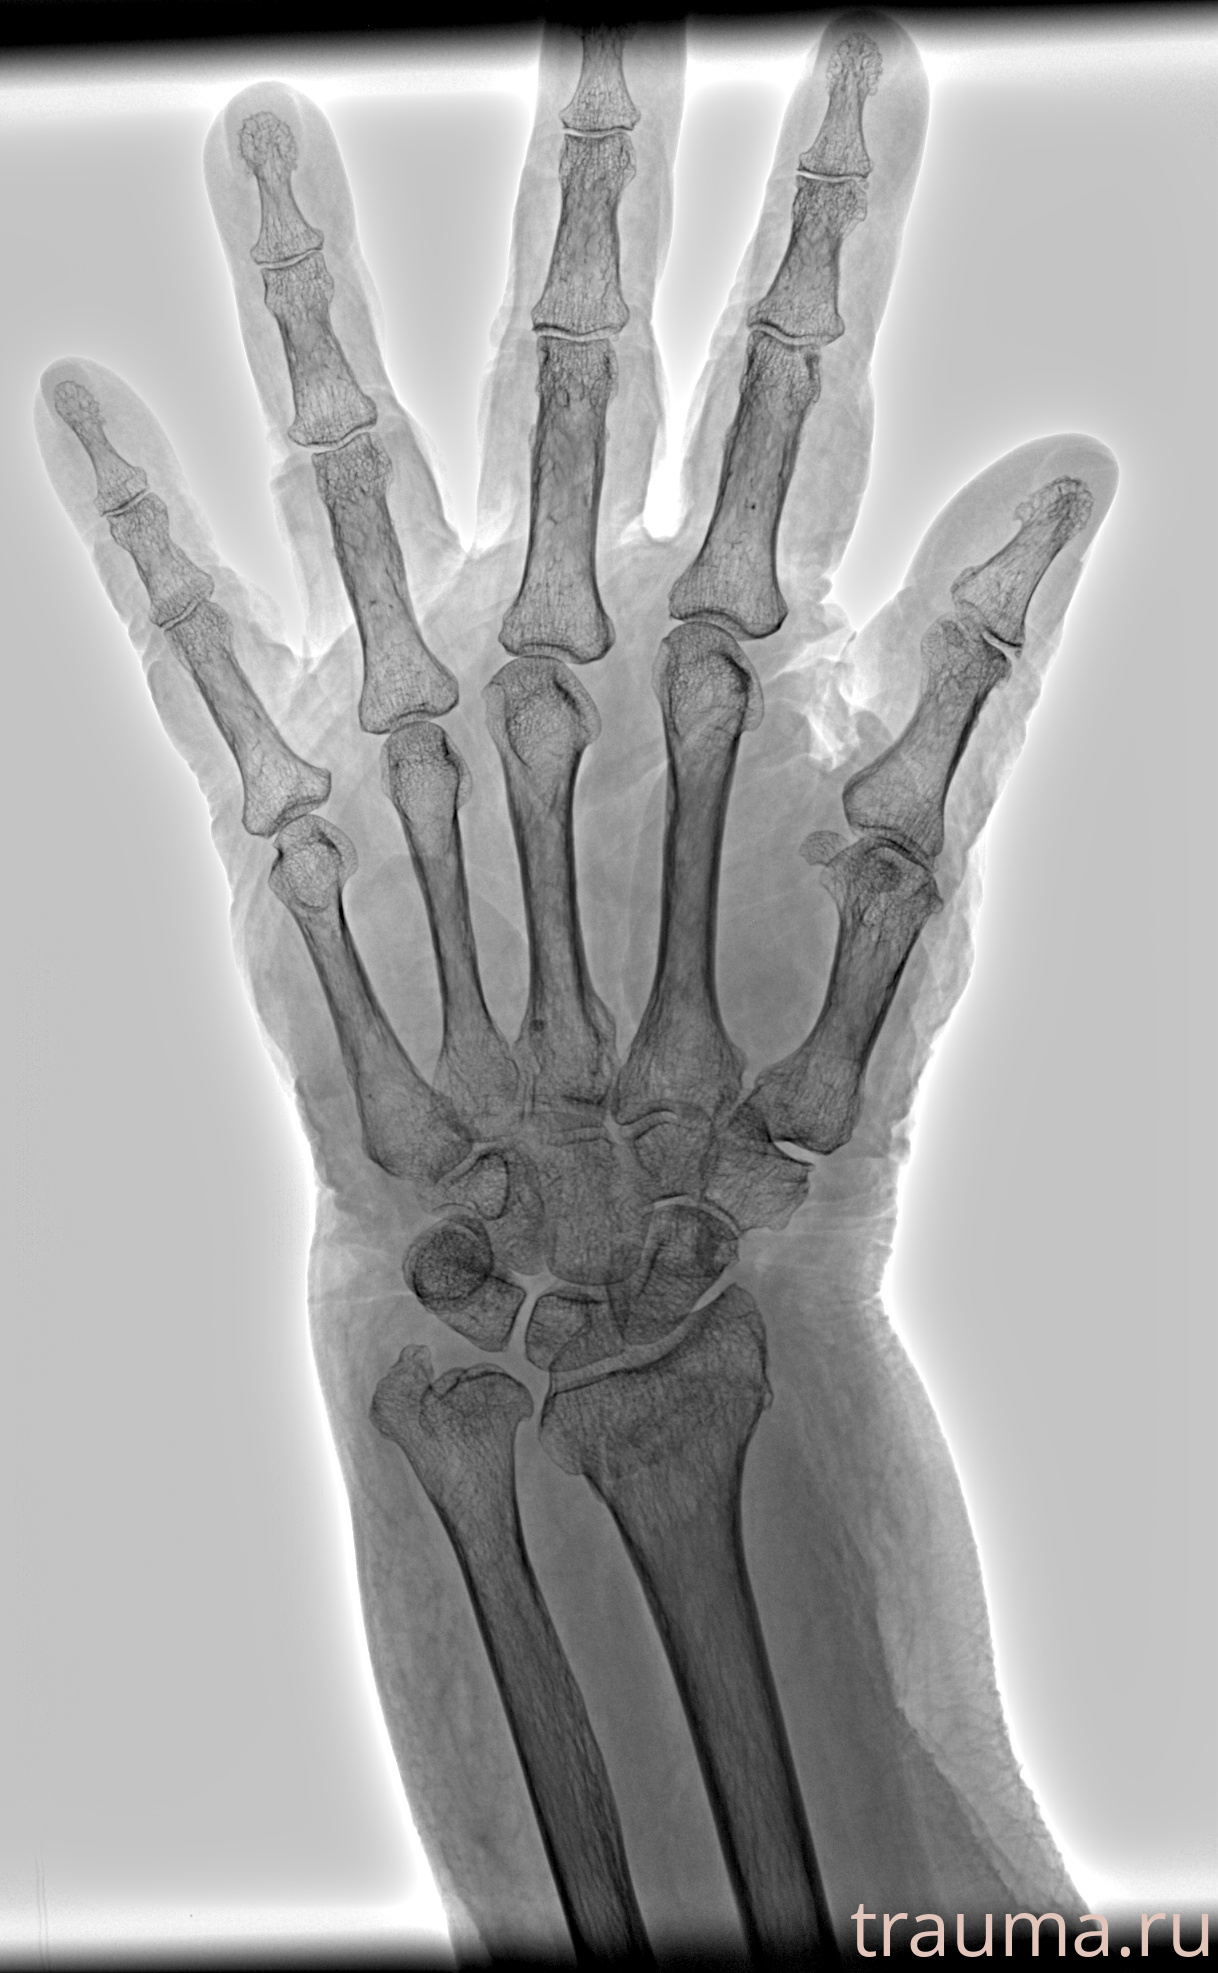

Рентгенограммы

Рентген на дому: по вашему адресу приезжает врач-рентгенолог, травматолог-ортопед с мобильным рентгеновским аппаратом, проводит диагностику травмы или заболевания, делает необходимые рентгенограммы, дает рекомендации по дальнейшему лечению. Получить качественные снимки в домашних условиях возможно благодаря уникальной методике, разработанной МосРентген Центром для института  Склифосовского